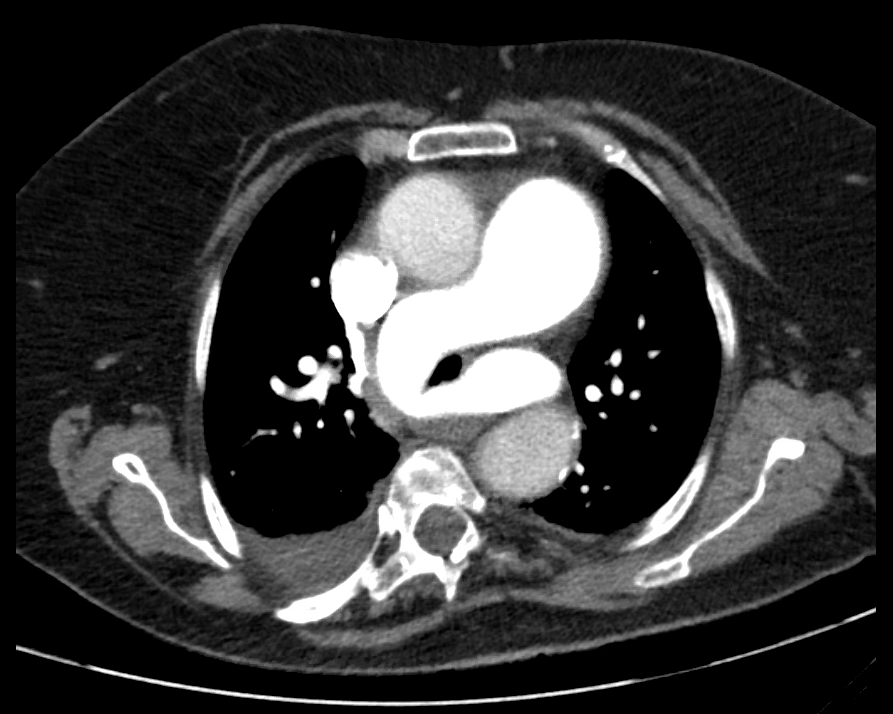

Case Presentation: 75-year-old female with past medical history of obesity (BMI 31.7 kg/m2), paroxysmal atrial fibrillation, hypertension, hypothyroidism, was admitted to the hospital for elective laparoscopic cholecystectomy. Patient tolerated the procedure without complications, however, post operatively, she was difficult to extubate due to hypercapnia of pCO2 of 100 mmHg in arterial blood gas. She was transferred to the surgical intensive care unit; her stay was complicated with an isolated episode of atrial fibrillation with rapid ventricular response which resolved with the use of beta blockers. Patient was successfully extubated 2 days after procedure, and was transferred to general medicine floors on post-op day 4 for management of atrial fibrillation. During hospitalization, the patient had several episodes of morning somnolence and occipital headaches which improved as the day progressed, morning venous blood gas analysis showed pCO2 of 95 and pH 7.21; additionally, patient experienced frequent episodes of hypoxia requiring supplemental oxygen, tachypnea, and tachycardia. Given her recent surgical procedure, episodes of tachycardia, and hypoxemia, she was deemed to have a moderate risk for pulmonary embolism based on Well’s Criteria, this prompted a CT angiogram of the chest. Result of the CT was significant for aneurysmal dilatation of the central pulmonary artery (PA) measuring 5 cm, and an anatomic variation of left pulmonary artery sling, with the left pulmonary artery arising from the posterior right pulmonary artery, coursing to the left behind the trachea and in front of the esophagus, narrowing the width of the trachea. Pulmonary medicine and thoracic surgery were consulted, patient was managed conservatively, and discharged with nocturnal BiPAP use.